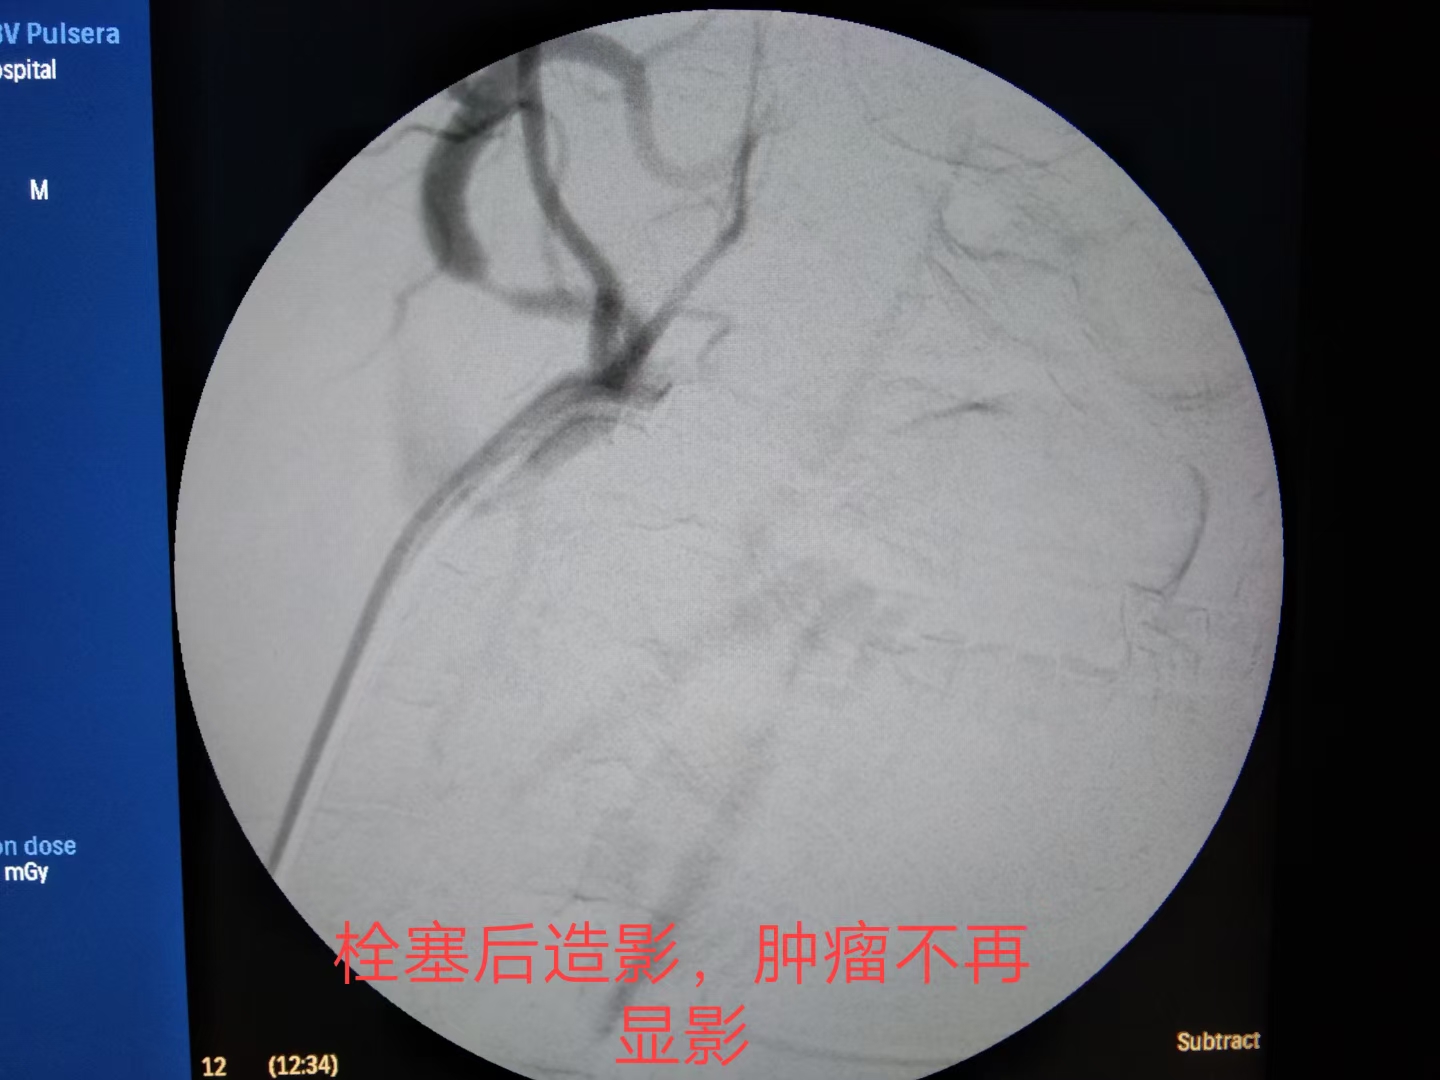

边扩容,输血,止血的同时,推入介入室。消毒、铺巾、穿刺、插管,造影。

最终,颗粒+弹簧圈完美栓塞。出血停止,患者生命体征平稳。